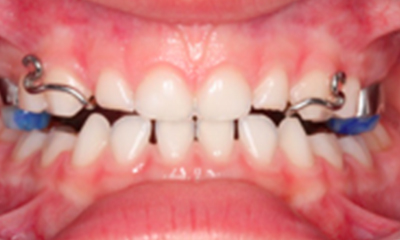

Caso 1

As imagens abaixo ilustram um caso de mordida cruzada posterior. Como se pode notar pelas imagens abaixo, a mordida cruzada posterior - quadrante direito do arco maxilar - foi corrigida com a ortodontia interceptativa.